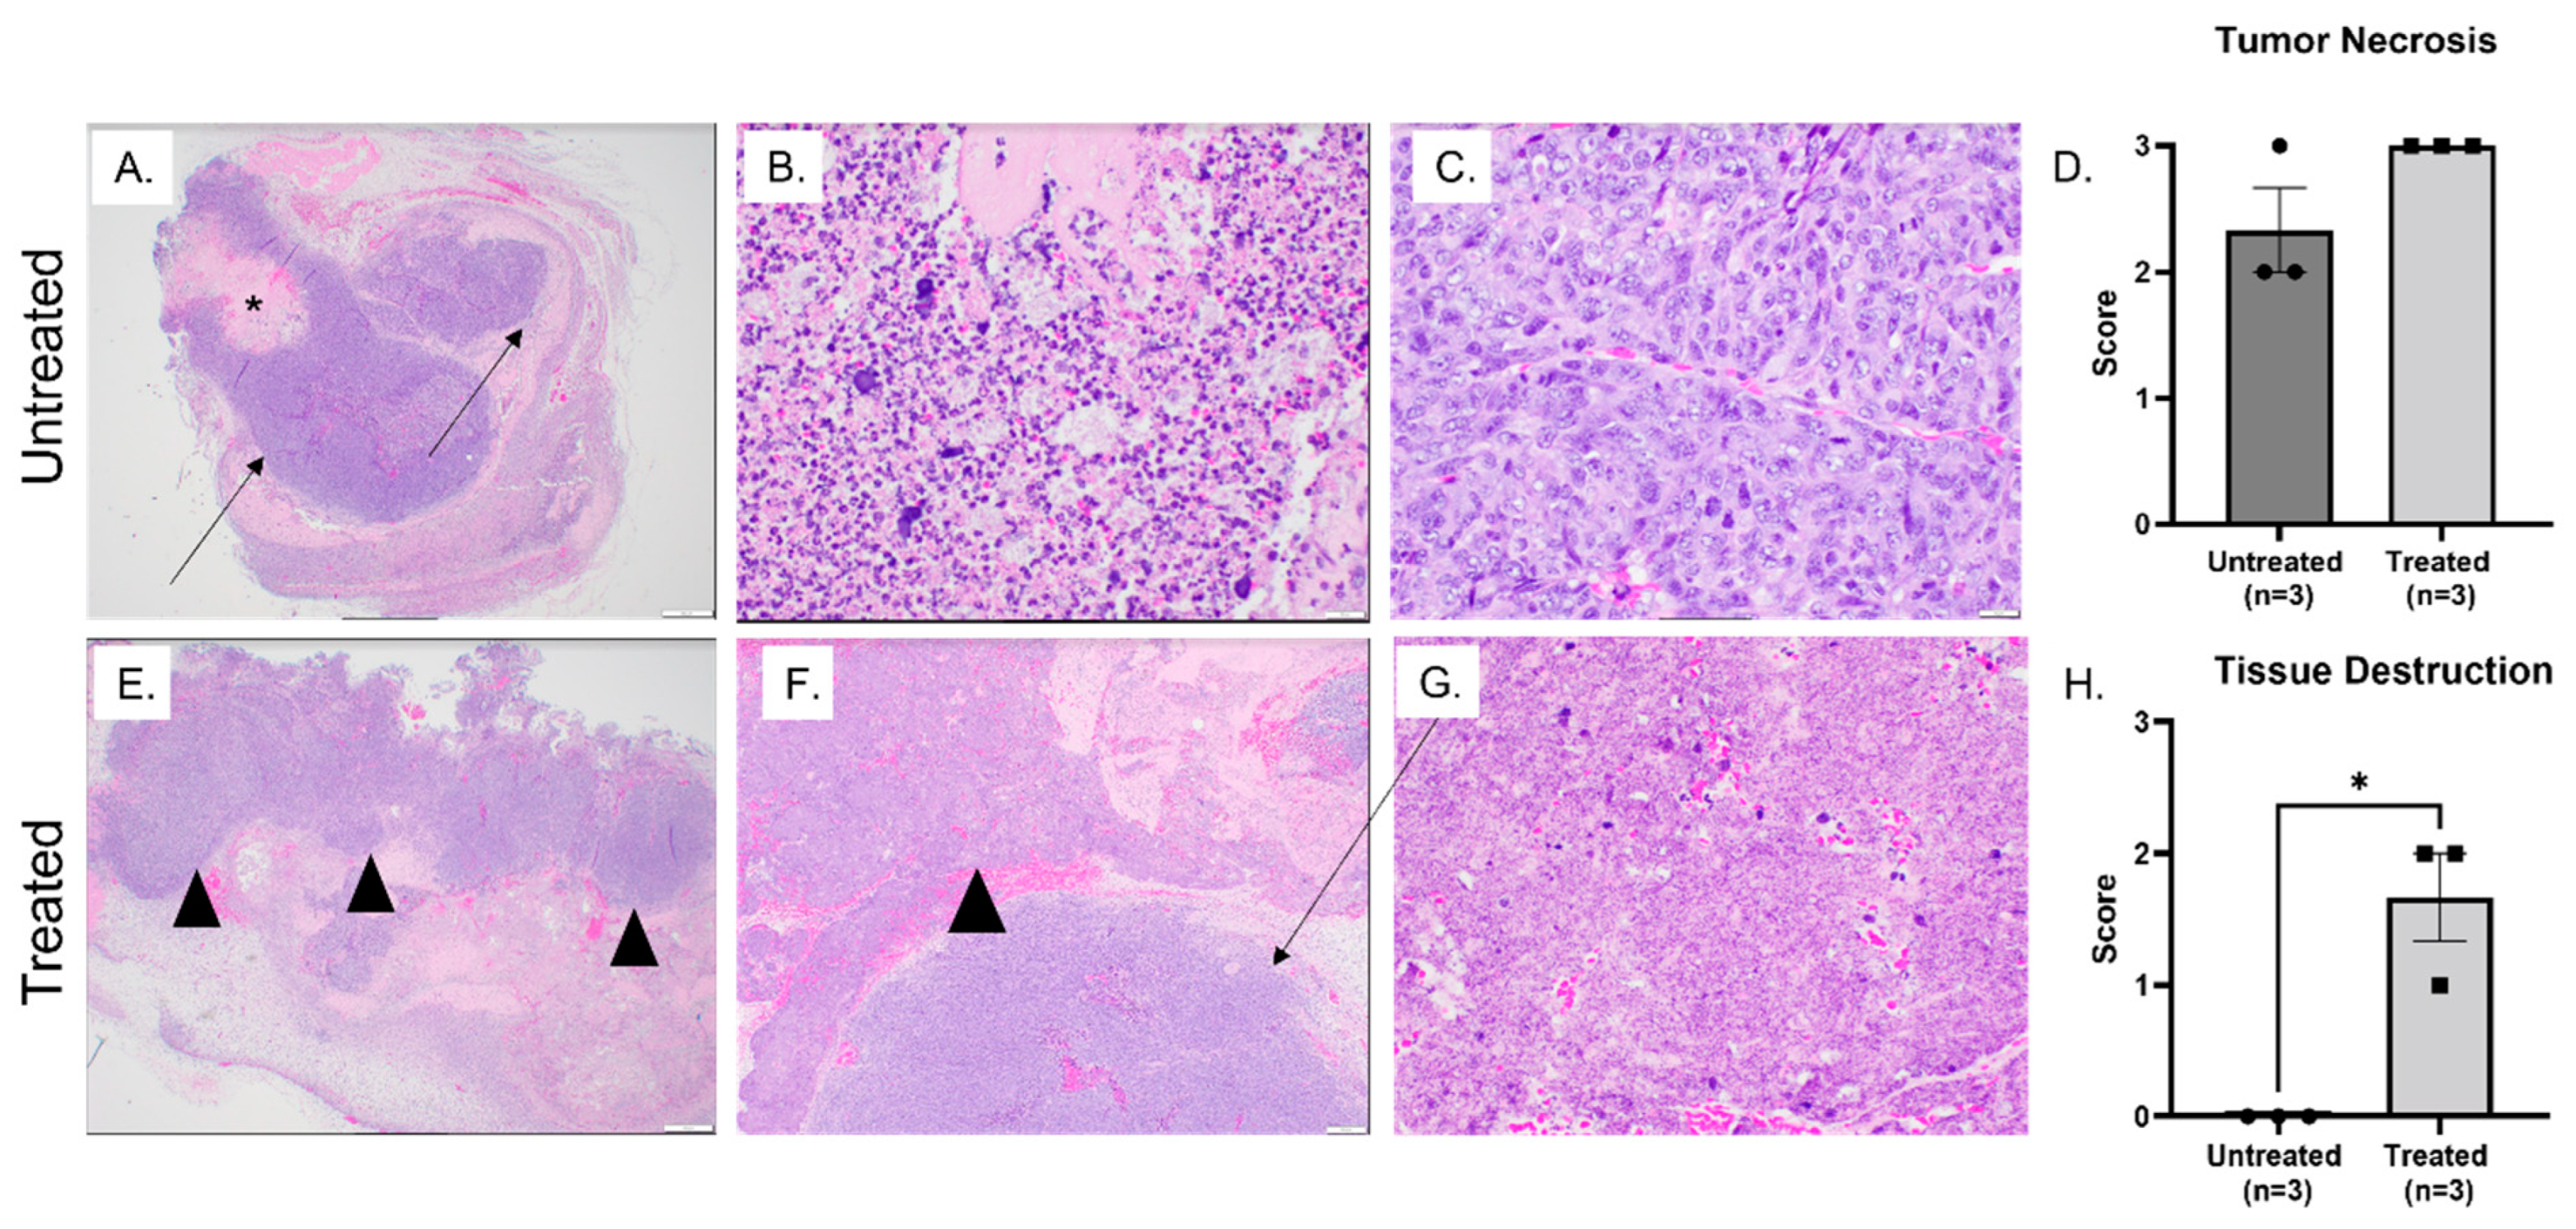

3.2. Histotripsy Ablation Resulted in Effective Tumor Tissue Destruction, Necrosis, and Immune Cell Infiltration